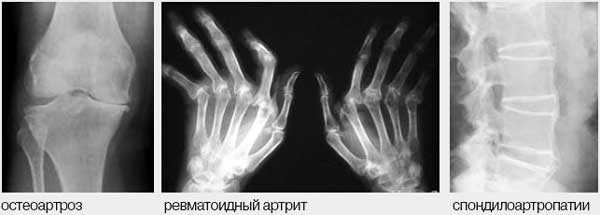

7. Асептические артриты разделяются на 2 большие группы - симметричные артриты при РА или диффузных болезнях соединительной ткани (ДБСТ) и на серонегативные артропатии, характерным для которых является асимметричное поражение преимущественно суставов нижних конечностей, вовлечение в процесс илеосакральных сочленений и позвоночника.

8. Наиболее часто поражение суставов и позвоночника связано с ОА, для которого характерно либо поражение 1-2 крупных суставов (локализованная форма), либо поражение мелких суставов с развитием узелков Гебердена и/или Бушара (узелковая или генерализованная форма), поражение позвоночника (спондилоартроз).

Рис. 1. Дифференциальный диагноз при болях в опорно-двигательном аппарате.